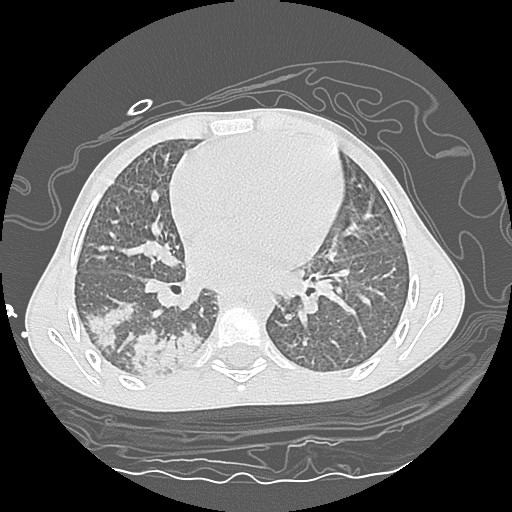

- Computerized tomography (CT) of chest.

| CT3 | CT4 | CT5 |